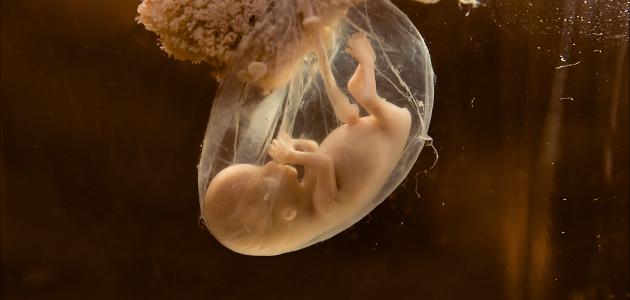

يسمى السائل الذي يحيط بالجنين بالسائل الأمنيوسي، فهو الذي يمد الجنين بالغذاء والحماية اللازمة عن طريق الكيس الأمنيوسي، الذي يحيط بهم جدار الرحم ليحميهم من التأثيرات الخارجية .

- يبدأ السائل الأمنيوسي بالتّكون بعد أسبوعين من التلقيح، وبعد عدة أسابيع يمتلئ السائل حول الجنين ليساعده في نموه، فهو يحتوي على البروتينات، والدهون، والكربوهيدرات، وكل ما يحتاج إليه الجنين في نموه، ومع استمرار نموّ الجنين يستمر السائل بالزيادة إلى أن يتمزق الكيس الأمنيوسي وينزل ماء المخاض .

- يتكون السائل الأمنيوسي من الأم والجنين معاً، ويحتوي على 99% من المياه، والباقي يتكون من المعادن، والمواد العضوية، وغير العضوية، والأهم أنه يحتوي على مادة ألفا بروتين الضرورية للجنين .

- يعمل السائل على حماية الجنين من التأثيرات الخارجية الواقعة على الرحم .

- يعمل على توفير مساحة جيدة ليتمكن الجنين من الحركة .

- يحافظ على درجة حرارة ثابتة في الرحم .